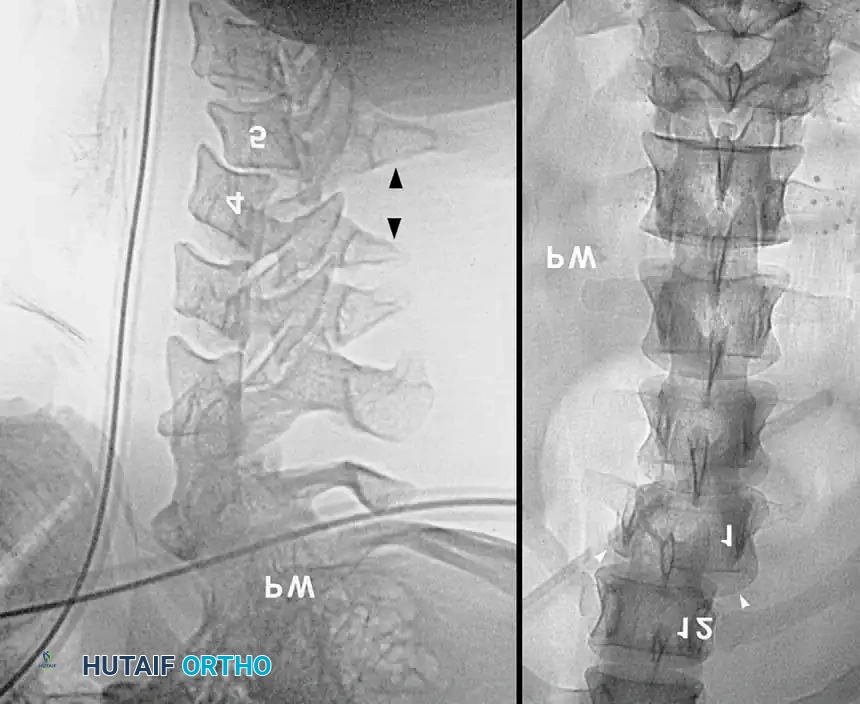

Computed Tomography (CT) and Magnetic Resonance Imaging (MRI)

Due to the limitations of plain radiography, high-resolution Computed Tomography (CT) with sagittal and coronal reconstructions has become the gold standard for the initial osseous evaluation of the spine in trauma centers. CT provides unparalleled detail of bony architecture, facet joint alignment, and the presence of retropulsed bone fragments within the spinal canal.

If a patient is unconscious, obtunded, or uncooperative, clinical clearance of the cervical spine is impossible. In these scenarios, a normal CT scan of the C-spine (C1-T1) is highly reliable for ruling out unstable osseous injuries. However, if the patient remains comatose or if there is a high suspicion of a purely ligamentous injury, spinal cord contusion, or epidural hematoma, Magnetic Resonance Imaging (MRI) is the definitive modality. MRI is exquisitely sensitive for evaluating the posterior ligamentous complex, intervertebral discs, and the spinal cord parenchyma itself.